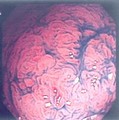

食管憩室

十二指肠球部溃疡

结肠癌

腺瘤

食管静脉曲张

食管炎

溃疡性结肠炎

锯齿状腺瘤

管状腺管腺瘤

小肠绒毛及淋巴滤胞

小肠绒毛

绒毛状腺瘤

肠息肉

直肠癌

增生性息肉